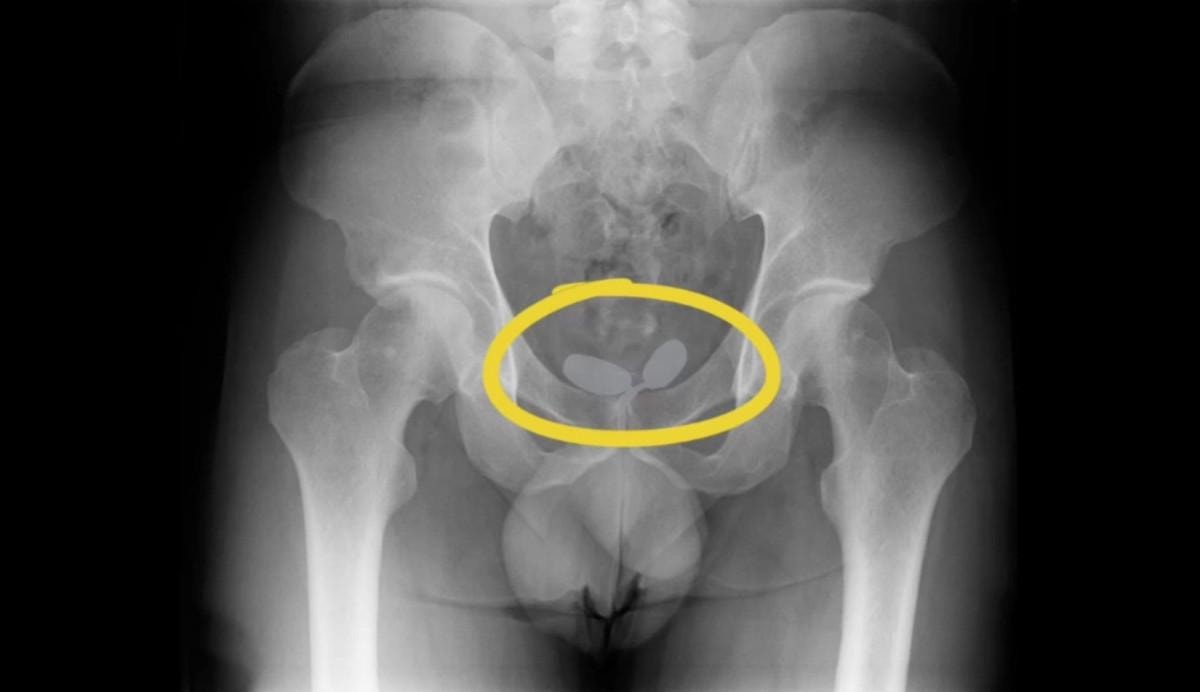

Yapılan röntgen muayenesinde, uyuşturucu kaçakçılarının akılalmaz oyunu ortaya çıktı.

Yapılan röntgen muayenesinde, Alman uyruklu kadının cinsel organında prezervatifler içerisine gizlenmiş uyuşturucular ele geçirildi.

Diğer Alman yabancı uyruklu erkeğin ise uyuşturucuları anüsüne gizlediği belirlendi.